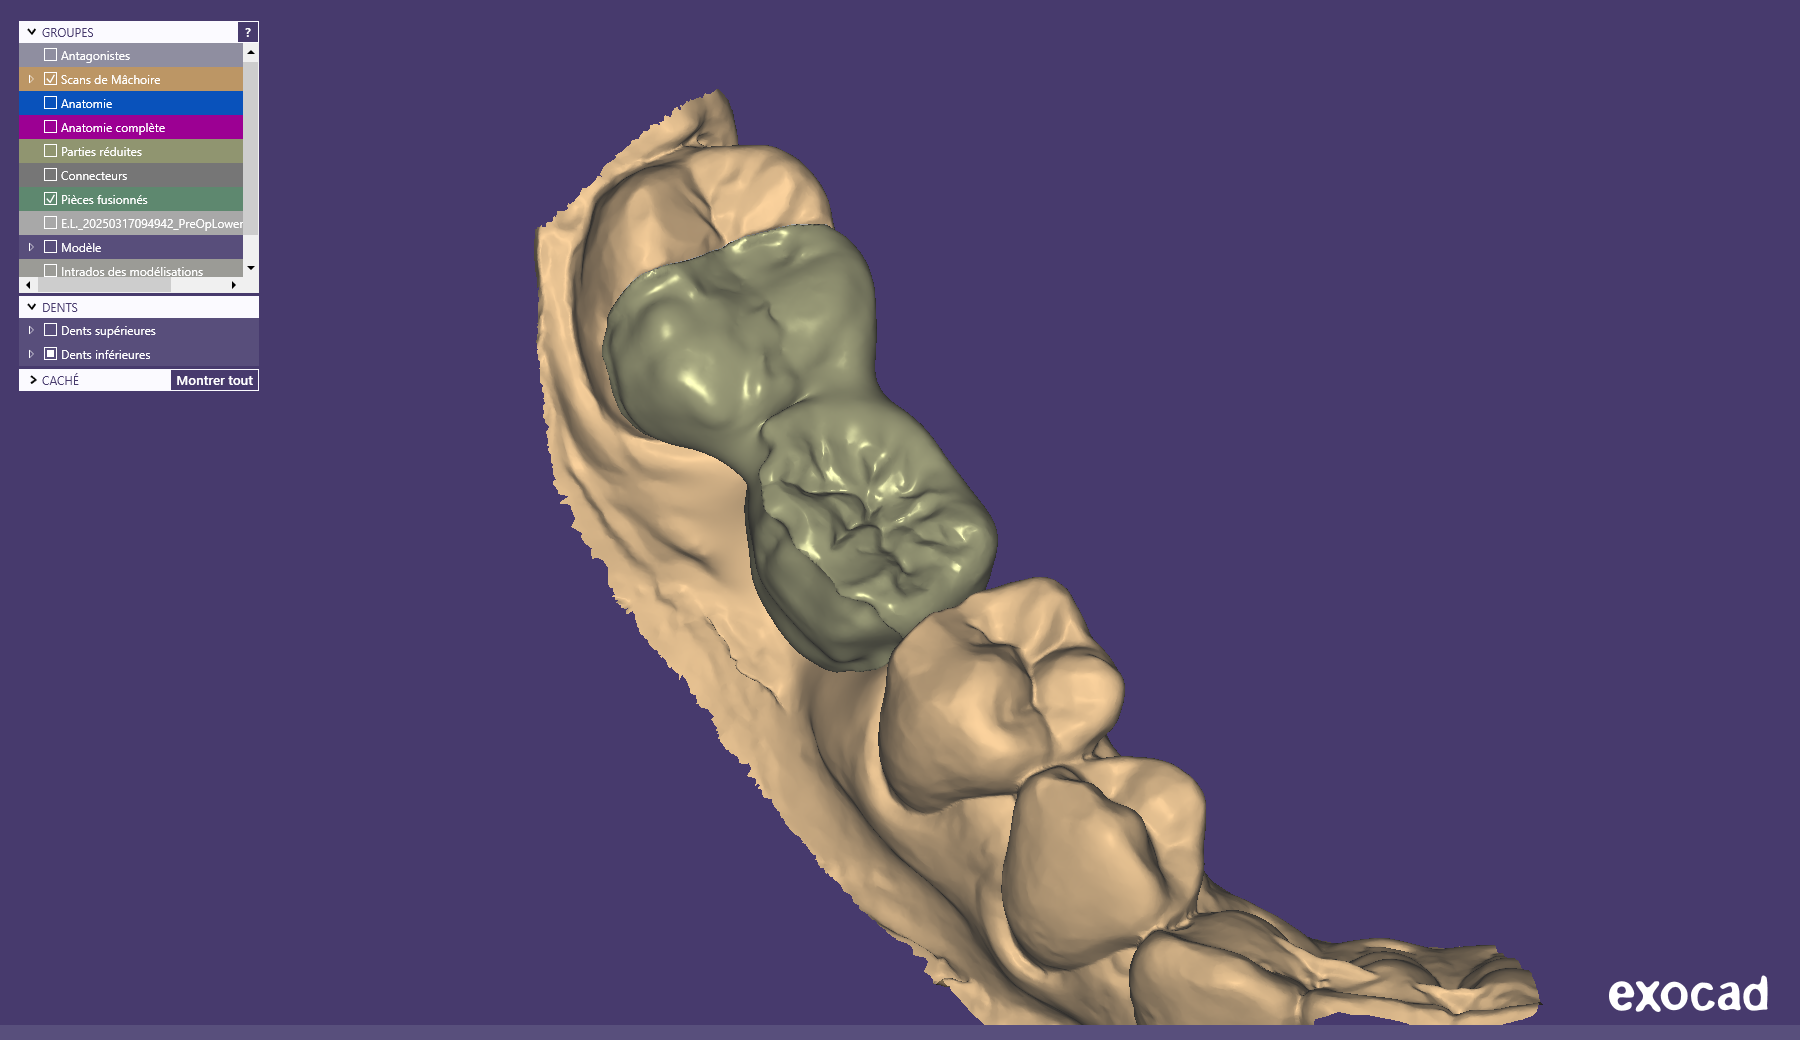

Relativement récents, les bridges collés cantilever postérieurs constituent une alternative fixe, fiable et véritablement minimalement invasive aux implants dans les secteurs postérieurs. Cette thérapeutique qui repose sur des indications bien précises est parfois débattue avec passion sur les réseaux sociaux ou dans les congrès scientifiques. Cependant des études cliniques existent, tout comme des recommandations validées dans des journaux internationaux. Leur succès repose sur des préparations et des principes biomécaniques rigoureux, pourtant simples à intégrer au quotidien. Cette intervention propose un guide clair et opérationnel incluant indications, étapes clés, protocoles d’adhésion et réglages occlusaux pour les mettre en œuvre avec confiance et reproductibilité.